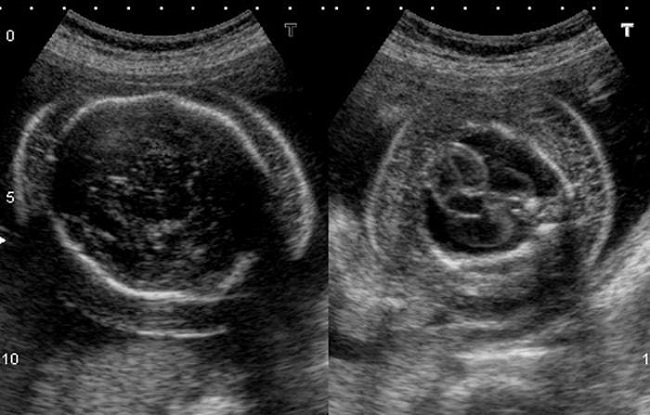

Janin dengan hydrops fetalis dapat mengalami gejala berupa pembesaran organ, seperti limpa, hati, dan jantung, serta adanya cairan di jantung dan paru-paru. Gejala ini umumnya dapat terdeteksi pada saat USG kehamilan.

Pemeriksaan ke dokter diperlukan jika ibu hamil memiliki rhesus yang berbeda dengan janin. USG kehamilan juga harus dilakukan pada usia kehamilan 18–22 minggu. Hal ini untuk mendeteksi hydrops fetalis lebih awal dan mencegah terjadinya komplikasi pada janin maupun bayi yang baru lahir.

- USG kandungan, untuk mengetahui penyebab gerakan janin yang berkurang dari biasanya, yang bisa menjadi salah satu gejala hydrops fetalis